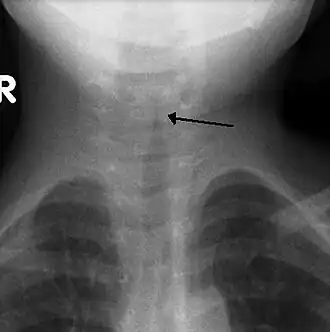

Pseudokroep (laryngitis subglottica of valse kroep) is een virale ontsteking van de bovenste luchtwegen, in de buurt van de stembanden. Meestal wordt deze infectie door een verkoudheid voorafgegaan.

Door de ontsteking zwellen de slijmvliezen rondom de stembanden op. Daardoor wordt het inademen moeilijker en kan benauwdheid optreden. Het ademen gaat vaak gepaard met een gierend geluid (= inspiratoire stridor). Het stemgeluid is meestal hees. Ook kan een stevige blafhoest voorkomen. De lichaamstemperatuur is normaal, of hooguit 38 graden.